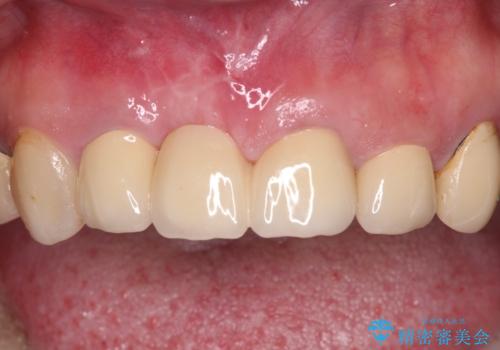

- 以前から前歯の根が折れていると言われていたものの放置しており、いよいよ痛みが気になってきたとのことで来院された患者様です。

検査の結果、右前歯の歯根が縦に破折していることが分かりました。

破折している歯は抜歯をし、歯肉が窪んでしまうので、傷口の治りを待って、歯肉移植を行うこととしました。

歯肉移植終了後、オールセラミックブリッジにて補綴することとしました。

歯肉移植により歯肉ラインや歯の形態を整えることができ、ブリッジによる補綴としたことで舞えば全体の色調を整えることができました。